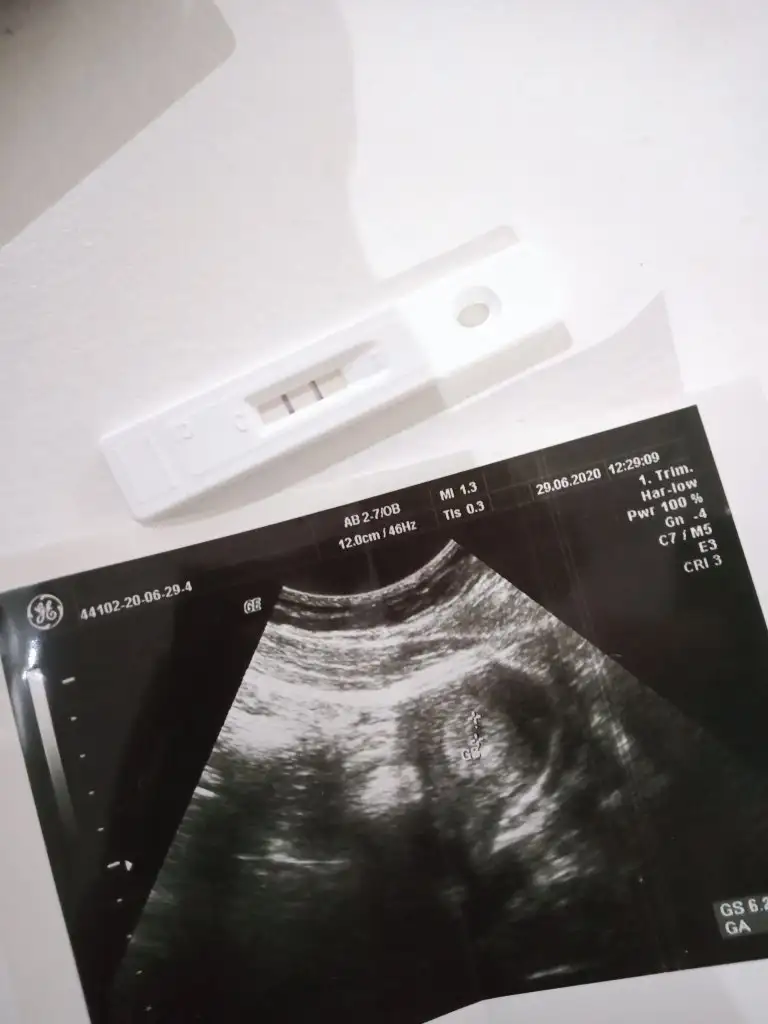

2020 Haziran Anneleri Gebelik, Ultrason, Testler, Gebelik Takibi

• 15935450621551140564515803518851.webp

15935450621551140564515803518851.webp

22,7 KB · Görüntüleme: 28